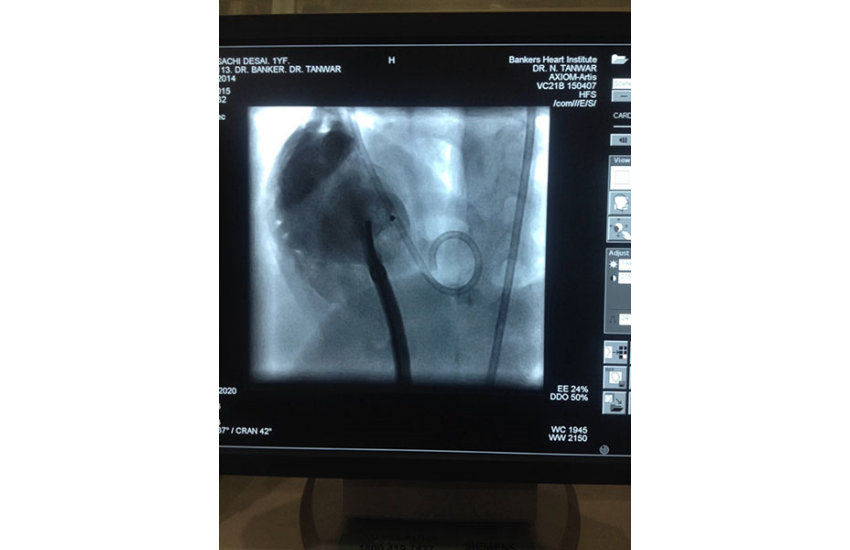

1 year girl with 7 kg weight successfully undergone Ventricular Septal Defect device closure.